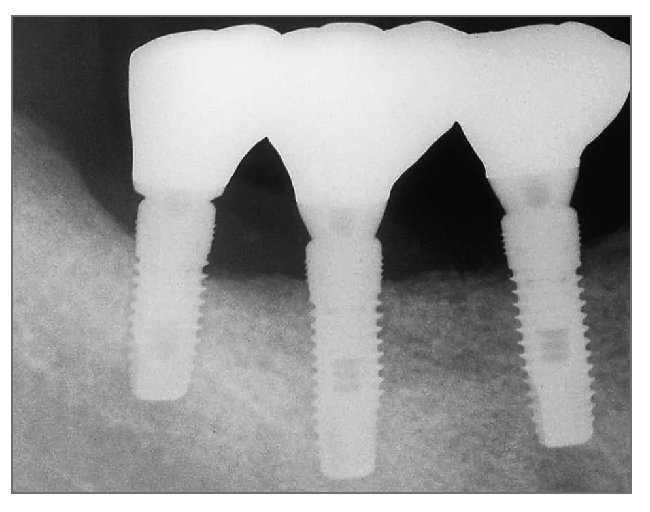

Un hombre de 44 años de edad se presentó en el Departamento de Periodoncia del Hospital Capital de las Fuerzas Armadas, Gyenggido, de Corea, para tratamiento de la pérdida de sus molares inferiores derechos (fig. 1). La historia clínica no presentaba datos de interés y el paciente no tomaba ninguna medicación que pudiera interferir con la curación de las heridas. El paciente fue remitido al Departamento de Prótesis para una evaluación más completa y planificación del tratamiento. Se le dieron explicaciones respecto a su estado actual, plan de tratamiento y procedimientos que realizar. Tras consultarlo con él se planificó un tratamiento con colocación de implantes e injerto óseo simultáneo. Se obtuvo consentimiento informado del paciente.

Figura 1 (izquierda). Caso 1. Imagen transversal de una tomografía computarizada antes del tratamiento.